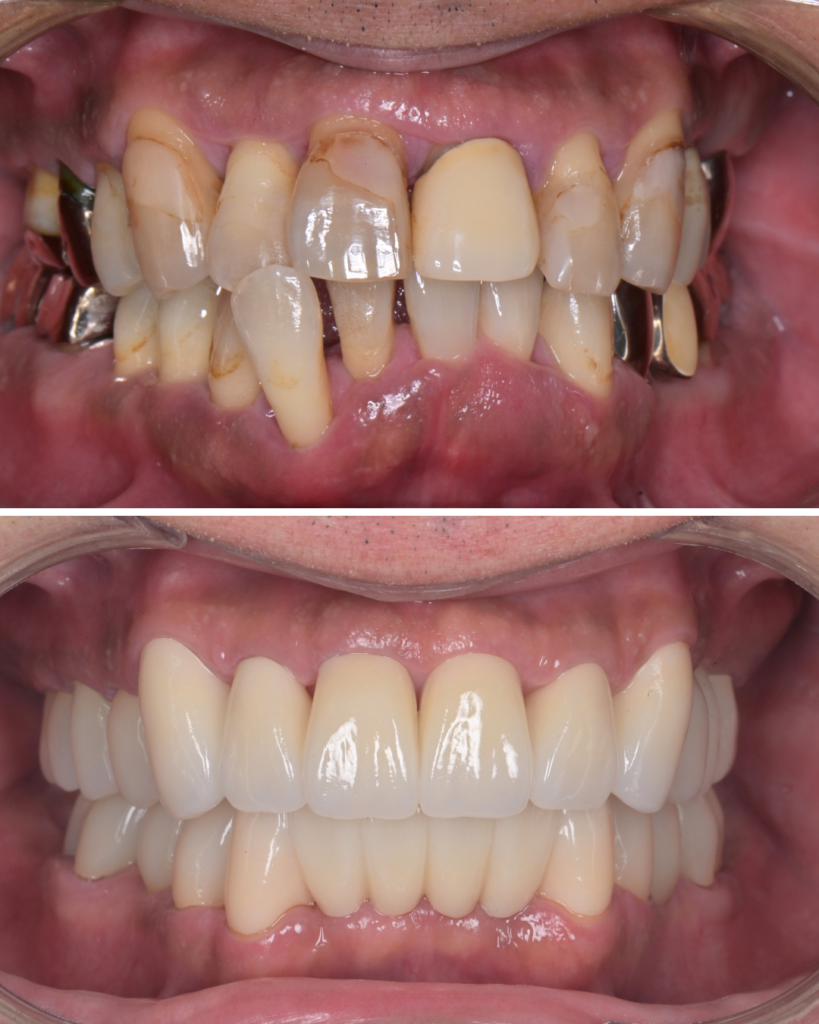

50代 歯周病 セラミック治療 ビフォーアフター

歯周病で歯がグラグラしていたため、歯列矯正は行わず、歯の状態を優先してセラミック治療を選択した50代の症例です。

歯を連結することで安定性を確保

- グラグラしている前歯は、セラミックで連結

- 見た目だけでなく、噛む力を分散し安定させる目的

歯並び・色・形を同時に改善できる

- ガタガタ

- 歯の長さの不揃い

- 被せ物の色の違い

を一度の治療計画で改善できるメリットがありました。